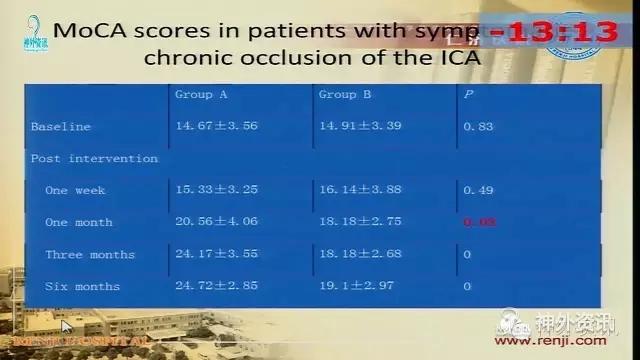

万杰清教授:慢性颈动脉闭塞再通技术及临床效果